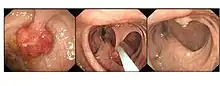

Polype colorectal

Les polypes du côlon forment un groupe très hétérogène de tumeurs bénignes du tube digestif, le terme de « polype » ne désignant qu'une élevure, une saillie visible à l’œil nu sur la muqueuse colorectale.

La plupart des polypes du côlon sont sporadiques. Les polypes du côlon ne doivent pas être négligés en raison du risque de développer un cancer du côlon et le risque que les polypes bénins du côlon se transforment au fil du temps en forme maligne[3]. Comme la plupart des polypes sont asymptomatiques, ils sont généralement découverts pendant un dépistage du cancer du côlon. Les méthodes de dépistage les plus courantes sont le toucher rectal, la sigmoïdoscopie (sigmoïdoscopie habituellement flexibles, à l'aide d'un endoscope flexible, mais plus rarement avec un endoscope rigide), l'endoscopie par capsule, le lavement baryté, la coloscopie et la coloscopie virtuelle[1]. Les polypes sont systématiquement supprimés au moment de la coloscopie soit avec une polypectomie[4], soit avec une pince à biopsie. Si un polype adénomateux est repéré avec la sigmoïdoscopie ou si un polype est trouvé avec toutes autres modalités de diagnostic, le patient doit subir une coloscopie pour l'ablation du polype. Même s'il n'y a généralement pas de risque de cancer du côlon dans les polypes de taille inférieure à 2,5 cm, tous les polypes découverts sont supprimés pour réduire la probabilité de développer un cancer du côlon. Lorsque les polypes adénomateux sont retirés, une nouvelle coloscopie est habituellement effectuée tous les trois à cinq ans[5].